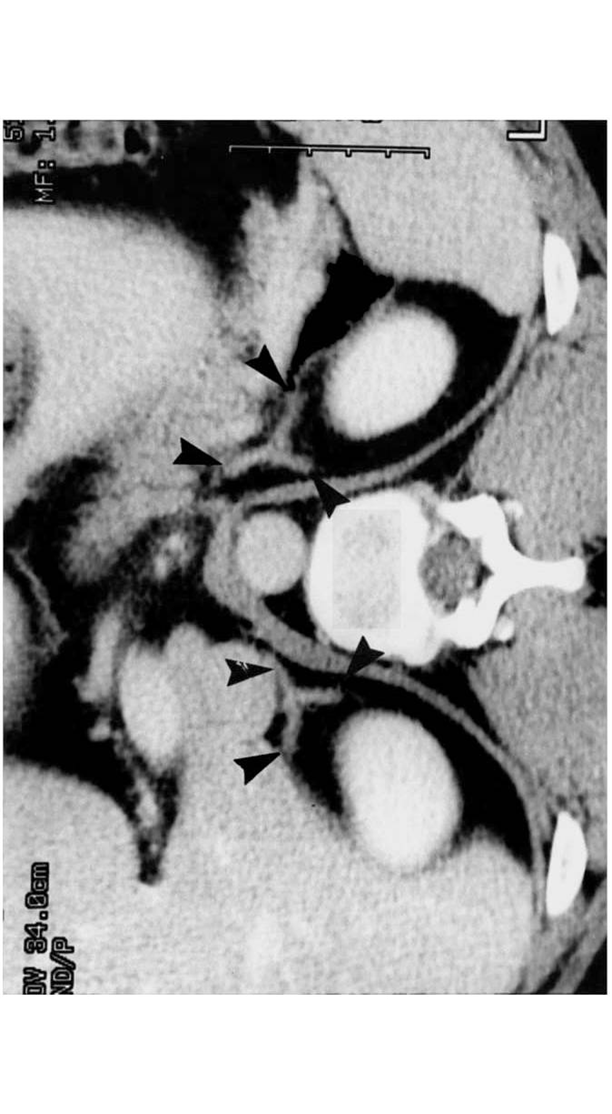

What do the adrenal glands look like on imaging? What is its blood supply?

On imaging, adrenal glands appear like a wish-bone shaped organ that sits anterior and medially to the kidneys